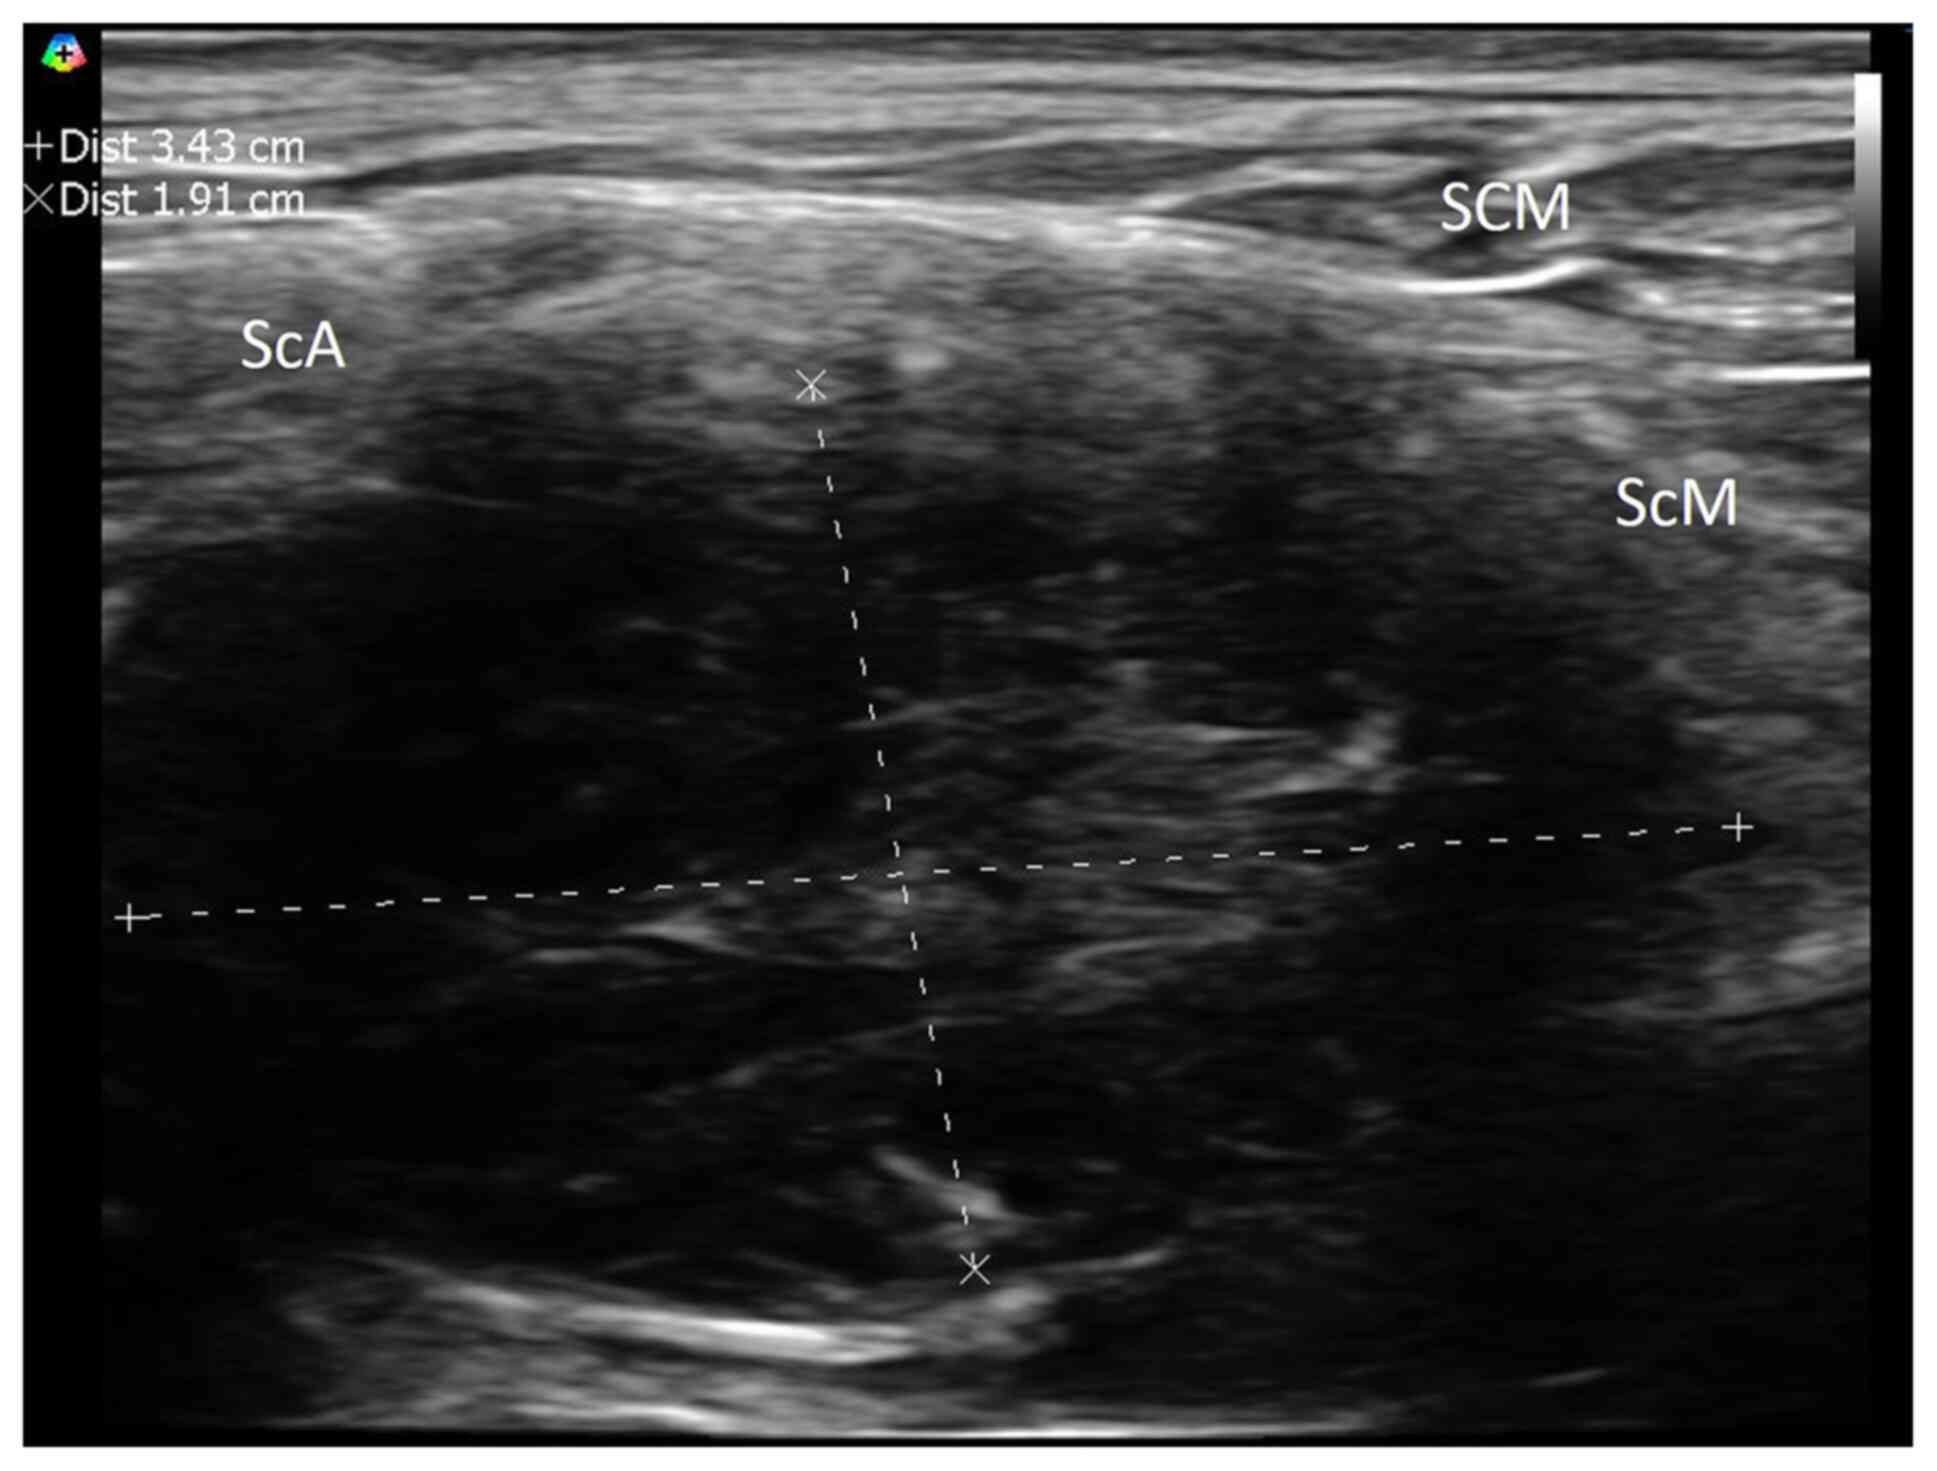

Subsequent examination using neuromuscular ultrasound revealed a

lesion localized to the left 7th cervical root (Fig. 1). Magnetic resonance imaging (MRI)

The present case presented with left neck and

shoulder pain, both subtle clinical signs commonly encountered in

clinical practice. Compared with previous cases, the present case

was atypical meningioma with brachial plexus involvement. The

abnormality detected during electrophysiological examination and

the neuromuscular ultrasound provided an indication that led to the

to the investigation of a tumor on the left cervical root.

Since the clinical features of extradural and

intradural meningiomas are not markedly different, in cases where

patients exhibit an inadequate response to conservative treatment

for shoulder pain, a comprehensive examination, including

electrophysiological studies and neuromuscular ultrasound, may

serve as valuable and cost-effective screening tools for detecting

structural lesions affecting the nerve root (27,28).

Neuromuscular ultrasound is a portable and real-time tool that is

useful for disease diagnosis in an outpatient setting (27,29,30).

However, MRI remains the gold standard for diagnosis and surgical

In the present case, regular clinical monitoring and

close long-term follow-up are required for further management. In

conclusion, detecting cervical extradural meningioma at an early

stage is challenging when a patient presents with non-specific

clinical symptoms or signs. Early detection is necessary for a

timely and effective treatment. This case demonstrated that

neuromuscular ultrasound is a valuable tool, aiding physicians in

identifying lesions over the nerve root and brachial plexus,

thereby enhancing the screening and diagnosis of meningiomas.